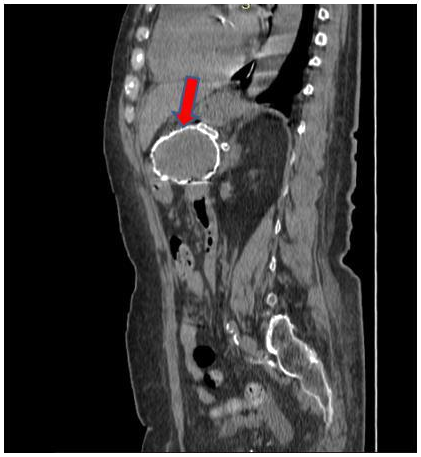

Hydatid Cyst of the Pancreas: A Highly Atypical Location

Sanae Jellal, Rachida Chehrastane, Jihane El Houssni, Sara Ez-Zaky and Tarik Salaheddine. 7(9): 01-04.